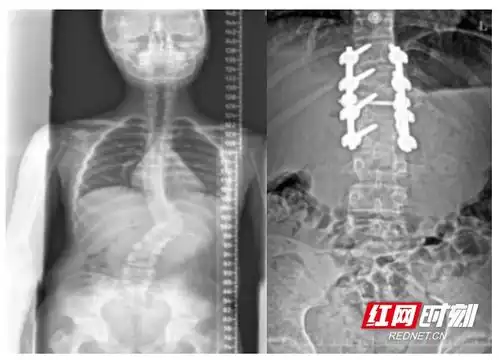

12岁安徽男孩脊柱畸形十年,终于在这挺直了腰

脊柱皇冠手术助12岁脊柱侧弯少年重获新生

男孩脊柱侧弯83度,手术后长高6厘米专家称若治疗不当会加重